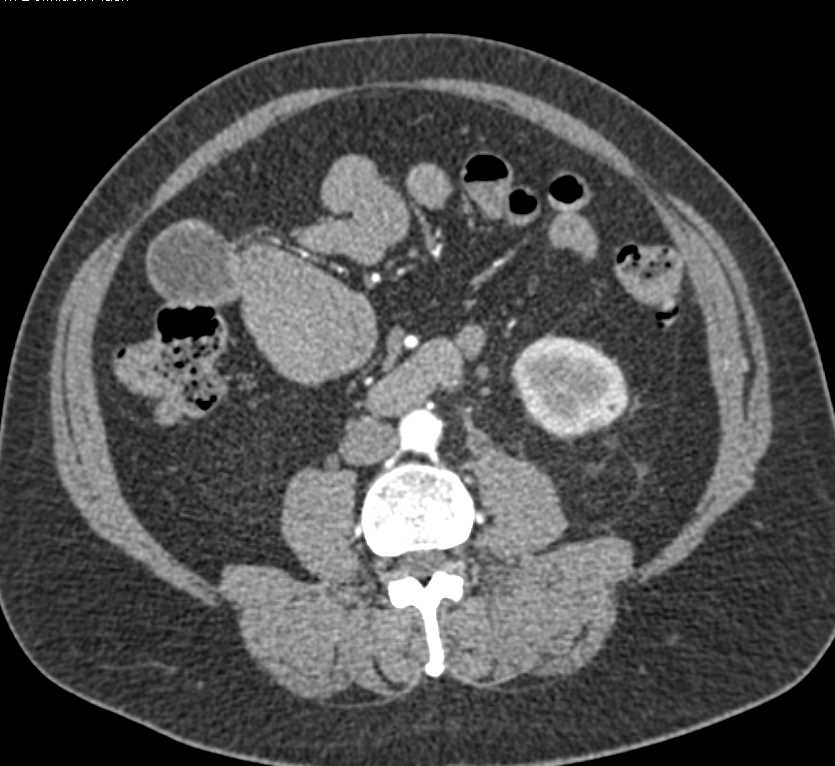

Lymphoma Involves the Left Kidney